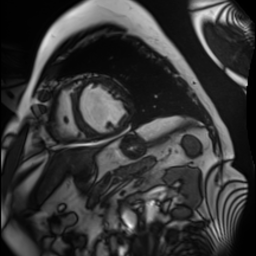

Synthetic Data Samples

Figure: Synthetic data generated by StyleGAN2-ADA for ACDC (top) and FIVES (bottom) datasets. Left to right: first 3 are original images, next 3 generated using 5% real data, last 3 using 10% real data.